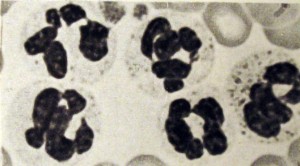

Cromatina sexual

Cromatina sexual (baqueta)

Cromatina sexual (Nódulos sésseis e pequenos grumos)

Cromatina sexual (Pequeno grumo)

Cromatina sexual (Raquete).